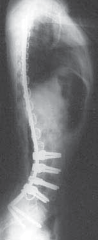

3. Final radiographs are taken to confirm coronal and sagittal alignment (

TECH FIG 4B–D

B.

AP radiograph of the patient in Figure 1 shows postoperative

correction of coronal plane deformity.

CDEFTECH FIG 4•

(continued)

Clinical photographs show correction of pelvic obliquity (

C

) and good sagittal plane alignment (

D

). Preoperative (

E

) and postoperative (

F

) lateral radiographs of patient with severe hyperlordosis corrected with unit instrumentation and pedicle screws used to correct lordosis in the apex of the deformity.